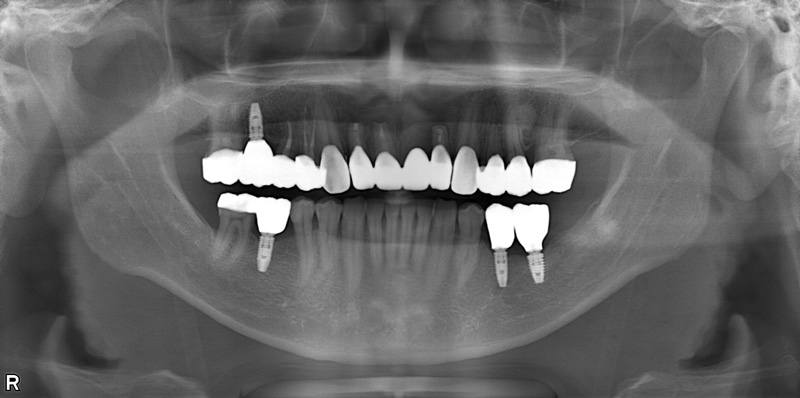

57歳男性

治療前

治療後

| 施術名 | インプラント治療 |

| 施術の説明 | インプラント治療とは、歯を抜いた所にチタン製の人工歯根を埋入し、新しく歯を入れる方法です。 |

| 施術の副作用 (リスク) | 腫れや疼痛を感じる、違和感を感じるなどの症状を生じることがあります。 |

| 施術の価格 | 53万円~+消費税 |